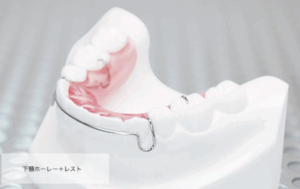

プレートタイプのリテーナー

最もよく使われるものです。取り外し式のもので、耐久性もあります。一方、表側にワイヤーが見えてしまいます。近年は、前歯の部分のみ、透明な素材で作成されたものも多く使われています。

↑ 代表的なプレートタイプリテーナー

当院では、患者様の元の歯並びや後戻りのリスクに合わせて、これらを組み合わせてご提案していますが、プレートタイプのリテーナーを装着していただく場合がほとんどになります。これらの特徴については、後日、詳しく記載した投稿をさせていただきます。